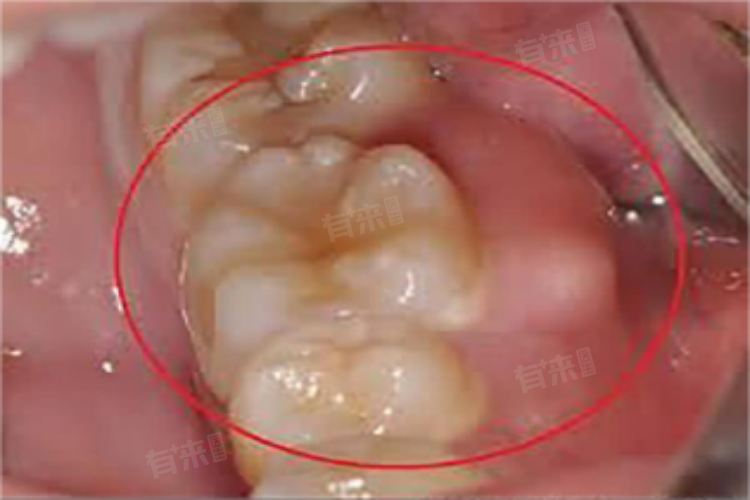

牙根发炎肿痛是一种常见的口腔问题,通常由于牙齿内有细菌与食物残渣堆积,刺激牙龈发炎而引发肿痛,可以选择调整饮食、药物治疗等方法进行处理。

3、冠周冲洗:针对牙根发炎肿痛,冠周冲洗是一种有效的治疗方法。在医生指导下,使用专业的冲洗液对牙齿周围进行冲洗,可有效清除牙齿内的细菌与食物残渣,促进炎症的消退和愈合。

4、根管治疗:如果牙根发炎肿痛症状持续不减或加重,可能需要进行根管治疗,根管治疗是通过清除牙齿内部的感染物质,并进行消毒和填充,以恢复牙齿的健康。这一治疗方法需要专业医生的操作,患者应遵医嘱按时复诊,确保治疗效果。